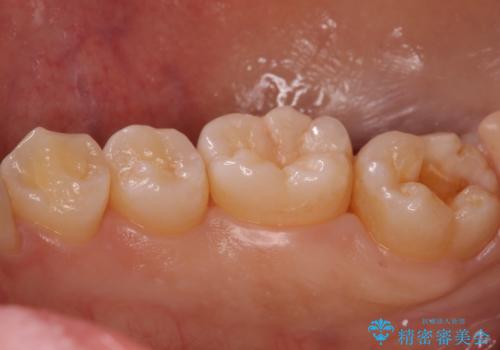

奥歯の黒ずみが気になる セラミックインレーでの治療

- 奥歯の黒ずみが気になるとのことで来院されました。

樹脂での治療も考えましたが、材料の劣化を避けるためにセラミックインレーでの治療をすることとなりました。

- 右下7 セラミックインレー 77,000円費用は治療当時の料金となります

セラミックは樹脂が含まれていないため劣化の面では非常に優れた材料です。